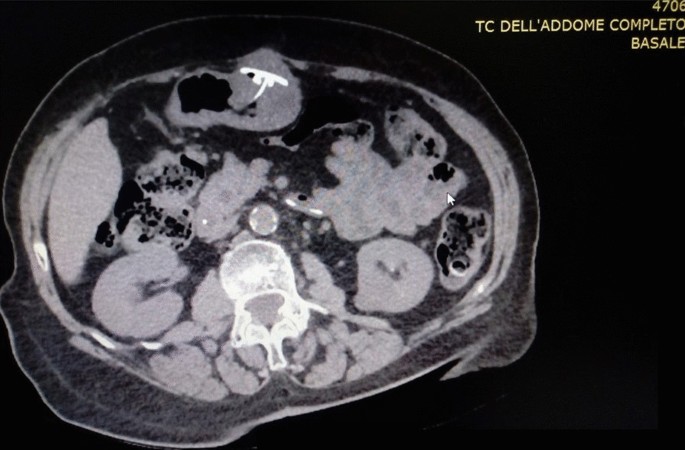

A 57 years old man affected by Advanced Parkinson’s Disease was selected for J-PEG placement to allow the continuous administration of LCIG in duodenum (AbbVie PEG polyurethane Tube 20 F). We obtained informed consent. He had a smoking history of 30/40 cigarettes per day for the past 30 years reporting a chronic cough, prevalently but not solely in the morning. On examination he appeared overweight (BMI = 29) with an abdominal fat distribution. Lung clinical examination revealed a barrel chest decreased brief sounds, with moderate inspiratory and expiratory wheezing, he used accessory muscles of respiration. There were signs and symptoms of chronic obstructive pulmonary disease (COPD); spirometry showed a ratio of forced expiratory volume in 1s (FEV1) and forced vital capacity (FVC) slightly lower than normal (65%); and low maximum expiratory flow (MEF was 80% at 25% and 50%). There were no absolute contraindication to place PEG tube. A pull-technique was used and a routine post insertion endoscopic confirmation of satisfactory PEG placement (AbbVie PEG polyurethane Tube 20 F) was performed at the end of the procedure. The PEG appeared successfully placed. Thirteen days later the tube was unable to infuse solution, there was a peritubal leak and the patient had abdominal pain with signs of edema and erythema of the tube insertion area. On the clinical examination we observed that during cough attack abdomen of our patient become prominent. Endoscopic evaluation showed that gastric mucosa covering internal gastrostomy site resulted in a complete closure of the orifice with visualization of only the J-tube extension. The internal bumper was not visible on the gastric wall but mucosa was ulcerated at the presumed site (Fig. 1). The patient underwent computed tomography (CT) (Fig. 2) of the abdomen, BBS was recognized and the device was removed by using a needle-knife assisted endoscopic dissection technique. After one week, following a thorough multidisciplinary evaluation due to the patient’s considerable anesthesiological risk, we positioned a new PEG-tube endoscopically in an area at a distance from the one used previously. Unfortunately, however, one month later the BBS presented again..Because the internal bumper was not visible endoscopically due to its dislocation into the abdominal wall, a microinvasive endoscopic needle knife-assisted approach was not feasible, and, therefore, we removed it surgically.

BBS is usually a late and rare complication of PEG occurring in 0.3–2.4% of the patients [1]. BBS usually appears no earlier than 4 months after PEG placement. Nevertheless it has been described a case of BBS after three weeks from tube placement [9]. In our patient, BBS occurred thirteen days after PEG insertion and then again after one month. The case of our patient suggests that COPD and chronic cough may represent a potential cause of BBS, even though the association between COPD with chronic cough and BBS as in our case does not necessarily imply a cause-effect relationship. Our case report underlines the important role of the traction performed by the respiratory movements in a patient with COPD with little airway obstruction, as evaluated by spirometry. The persistent cough produced a traction of the PEG tube and a bumper compression which in turn lead to gastric wall erosion. We cannot completely rule out the possibility that too much tension was placed on the bumper during PEG tube insertion or that there had been a lack of appropriate management of the tube. The first time, after thirteen days from the first positioning, there was a displacement corresponding to a type 3 BBS because the internal bumper appeared total visible at mobilization. The second time, after one month from the second PEG placement, a deep type 4 BBS occurred. This is according to Richter-Schraq HJ et al. who described 4 types of BBS: in type 1 the internal bumper is outside the body or in the subcutaneous tissue; in type 2 the internal bumper is partially visible in gastric lumen; in type 3 the internal bumper is not visible in the gastric lumen and is in the most superficial layers of the gastric wall; in type 4 the internal bumper is not visible in the gastric cavity and is in the deeper layers of the gastric wall [7]. BBS is a dangerous major complication of the PEG placement because it may cause infection, necrotizing fasciitis [3, 10], peritonitis and consequently septic shock with a fatal outcome [8]. Absolute contraindication to PEG placement are pharyngeal and esophageal occlusion for pull technique, active serious coagulopathy, hemodynamic instability, sepsis, severe ascites, peritonitis, peritoneal carcinomatosis, portal hypertension with gastric varices, total gastrectomy [1, 11]. Our patient had none of these absolute contraindications. Moreover some studies associated COPD at a higher risk of fatal outcome due to an increased susceptibility of COPD patients to develop gastroesophageal reflux disease that is strictly associated to a higher aspiration pneumonia risk, rather than a higher risk of BBS rising [12]. We believe that COPD with chronic cough may cause the displacement of the internal bumper thus causing BBS. Therefore, in case of a complication such as BBS it is important to have a radiologic evaluation in order to better assess the problem and possibly solving it through a surgical approach.